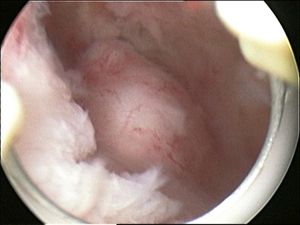

- Submucosal fibroids are most common type, located in the muscle beneath the endometrium of the uterus and distort the uterine cavity; even small lesions in this location may lead to bleeding and infertility. A pedunculated lesion within the cavity is termed an intracavitary fibroid and can be passed through the cervix.

- In a hysteroscopic myomectomy (also called transcervical resection), the fibroid can be removed by either the use of a resectoscope, an endoscopic instrument inserted through the vagina and cervix that can use high-frequency electrical energy to cut tissue, or a similar device.